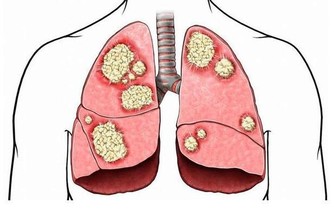

事實是,失明人口中,高度近視已經高居失明的第二大原因。日本及中國大陸在這一兩年的研究結果顯示,高度近視的視網膜黃斑退化也已經是老年人失明的第二大原因。甚至在日本,年輕成年人單眼失明的第一大原因,就是高度近視造成的,所以近視當然可怕。

你一定會好奇,造成失明的第一大原因究竟是什麼?答案是白內障。目前白內障是可以治療的,只要摘除白內障,置換人工晶體,大部分人的視力都會得以恢復。

但近視的可怕之處也在於此:高度近視引起視網膜黃斑退化所導致的失明,就算是再高明的眼科醫生也愛莫能助。